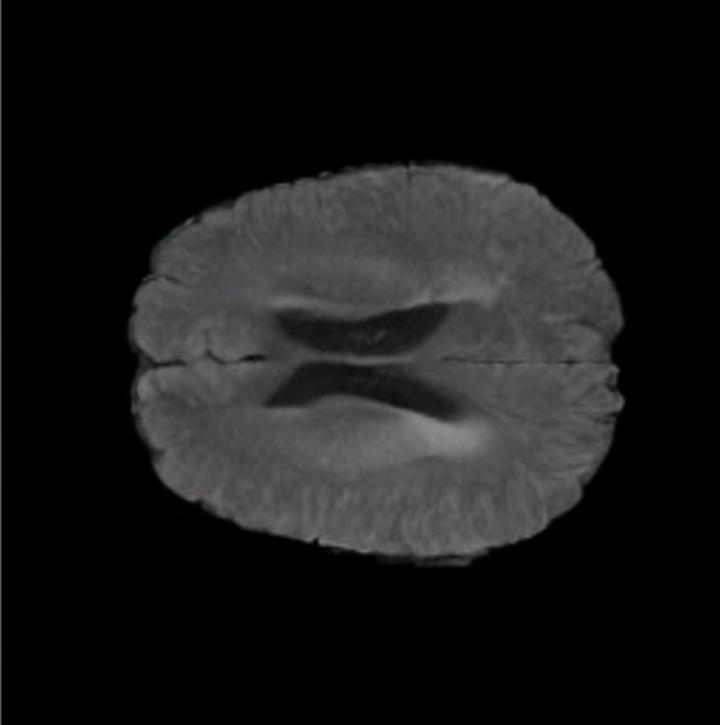

Notably, X-Diffusion achieves sota dB for a few input slices while baselines require more than 60 input slices to achieve similar performance (Figure 7). The margin is more than 12 dB PSNR for the 1-slice input in both the BRATS and the UK Biobank benchmarks (see Table 1 and Figure 6). For reference, two randomly sampled MRIs from the UK Biobank would have a PSNR of 15.95 dB 0.36 (on 4800 randomly sampled examples). The slices from 3D reconstructed volumes at varying depths and axis of rotation visually match the ground truths (see Figures 5 and Figure 4). We also plot the error map (Figure 4) of such X-Diffusion generations to highlight the differences with the ground truth MRIs.

Tumour Information Preservation. For the brain tumor segmentation, we use a Swin UNETR model[27, 70], trained with random rotation, and intensity as data augmentation. In Figure 5, we highlight the tumor profiles of the generated MRIs compared to the ground truth tumour profile. In the test set with human ground-truth annotations (), the real MRI Dice score is 85.15 while the generated MRIs from a single slice have a dice score of 83.09. This shows how the generated MRIs indeed preserve the tumor information and can act as an affordable and informative pseudo-MRI, before conducting an actual costly MRI examination in hospitals.

The comparison of generated MRIs versus reference MRIs suggests a nearly perfect preservation of brain volume (in mm3) with median volume of reference MRIs of versus generated MRIs (see an example of brain generation in Figure 11).